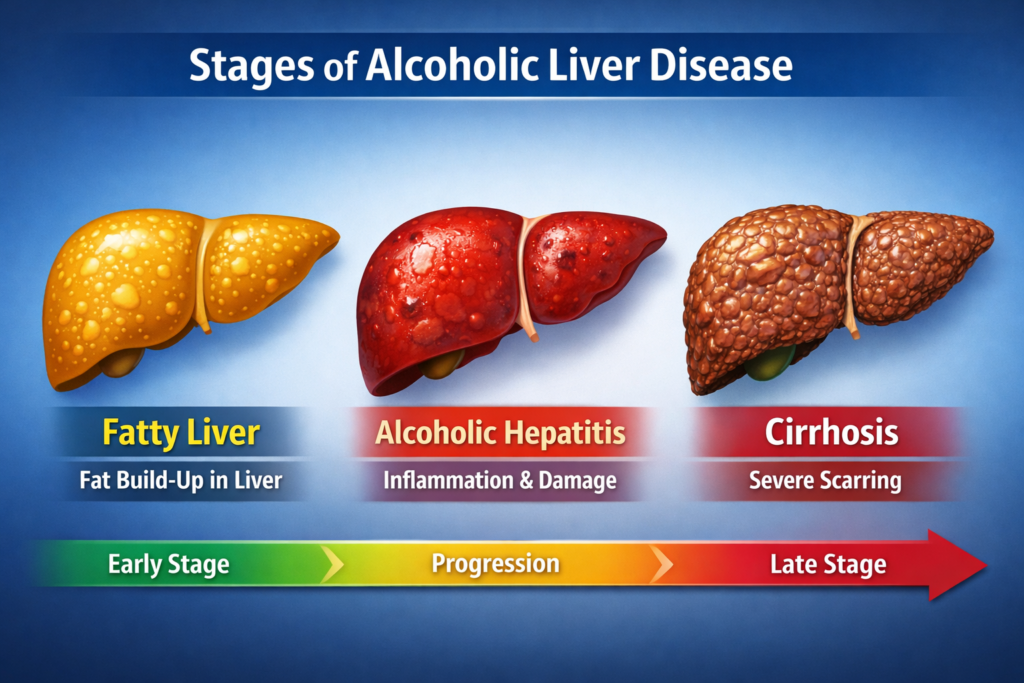

Looking for Hepatitis C treatment in Hyderabad? Dr Rahul Dubbaka offers advanced antiviral therapy with 95%+ cure rates at People’s Hospital, Pragathi Nagar. Book your consultation today at +91 9100921514. Hepatitis C is a viral infection that primarily affects the liver and can silently damage it over time. If left untreated, it may lead to serious complications such as cirrhosis, liver failure, and even liver cancer. The good news is that with modern medical advancements, Hepatitis C is now highly curable with effective antiviral medications.

Over time, chronic Hepatitis C can cause progressive liver inflammation, leading to fibrosis (scarring), cirrhosis, and increased risk of liver cancer.

Complications of Untreated Hepatitis C

If not treated, Hepatitis C may lead to:

Liver cirrhosis

Liver failure

Portal hypertension

Ascites

Liver cancer (Hepatocellular carcinoma)

Early treatment prevents these complications and improves life expectancy.

Importance of Early Treatment

Many patients delay treatment due to lack of symptoms. However, early treatment:

Prevents irreversible liver damage

Reduces risk of transmission

Improves overall quality of life

Offers complete cure in most cases

Timely intervention makes a significant difference.